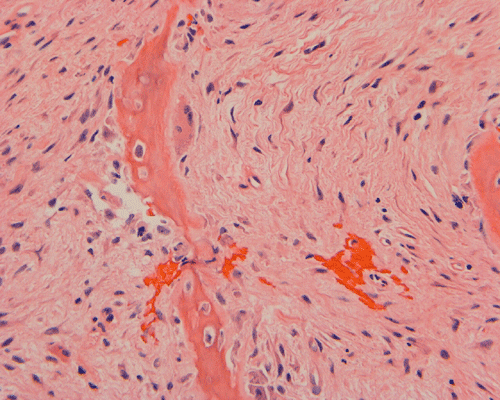

Pathology of the case: The specimen consists of multiple small pieces of irregular tissue fragments obtained by curretage. Histologically, the lesion tumor consists of bland spindled cells embedded in a collagenous matrix and arranged in a storiform pattern with frequent hemorrhage (Panel B). Entrapped residual bone associated with foci of osteoclastic type giant cells are present (Panel C). A scant number of epithelial islands are also scattered within this spindle cell background (Panel D, E, and F). On high magnification, no significant nuclear atypia or pleomorphism is noted in either the spindle cell or epithelial cell components. In other parts of the specimen, the spindle cell tumor is admixed with spiculated fragments of woven bone rimmed by osteoblasts (Panel H, I, and J). Small islandsIt of epithelial cells are also noted in these areas (Arrow in Panel H).

On immunohistochemistry, the epithelial islands are positive for cytokeratin AE1 and AE3 (Panel K and L). Both the spindle cell component and epithelial cells are positive for vimentin (Panel M).